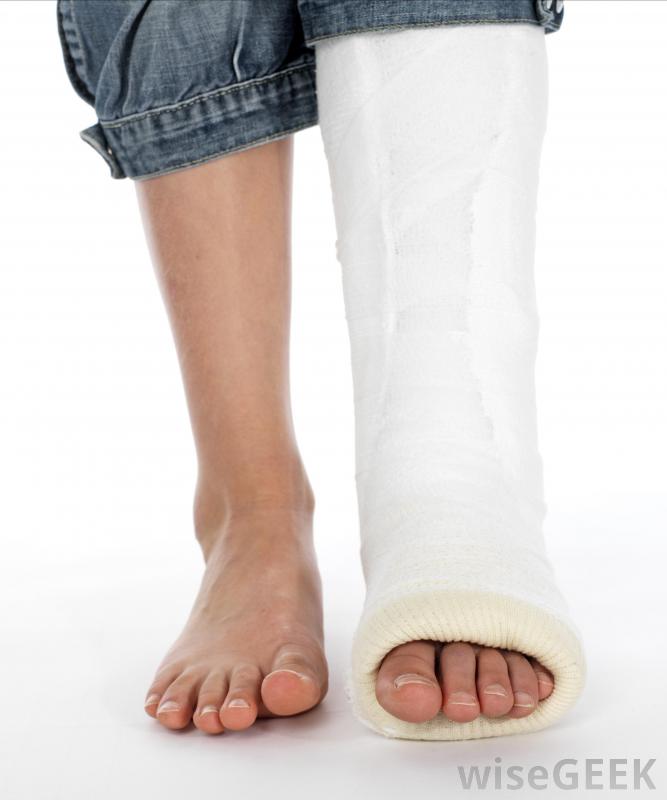

石膏通常用于治疗撕脱性骨折。当试图评估如何治疗撕脱性骨折时,它有助于了解这种类型的损伤是什么。在这种形式的损伤中,韧带或肌腱通常是在剧烈的运动中,如投掷或跳跃时,从骨头上拉出来。当这种情况发生时,韧带或肌腱,因为它附着在骨头上,所以可以带走一块骨头